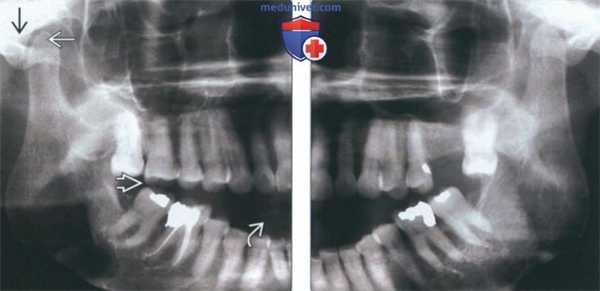

(Слева) На сагиттальной реформатированной КЛКТ определяется анкилоз левого мыщелка. Мыщелок склерозирован, суставное пространство отсутствует в зоне слияния. Височная кость неровная, склерозированная. Суставная ямка уплощена, суставное возвышение отсутствует.

(Справа) На панорамной рентгенограмме определяется костный анкилоз левого ВНЧС. Суставное пространство не визуализируется, форма мыщелка плохо различима. Венечный отросток удлинен, антегониальная вырезка углублена.